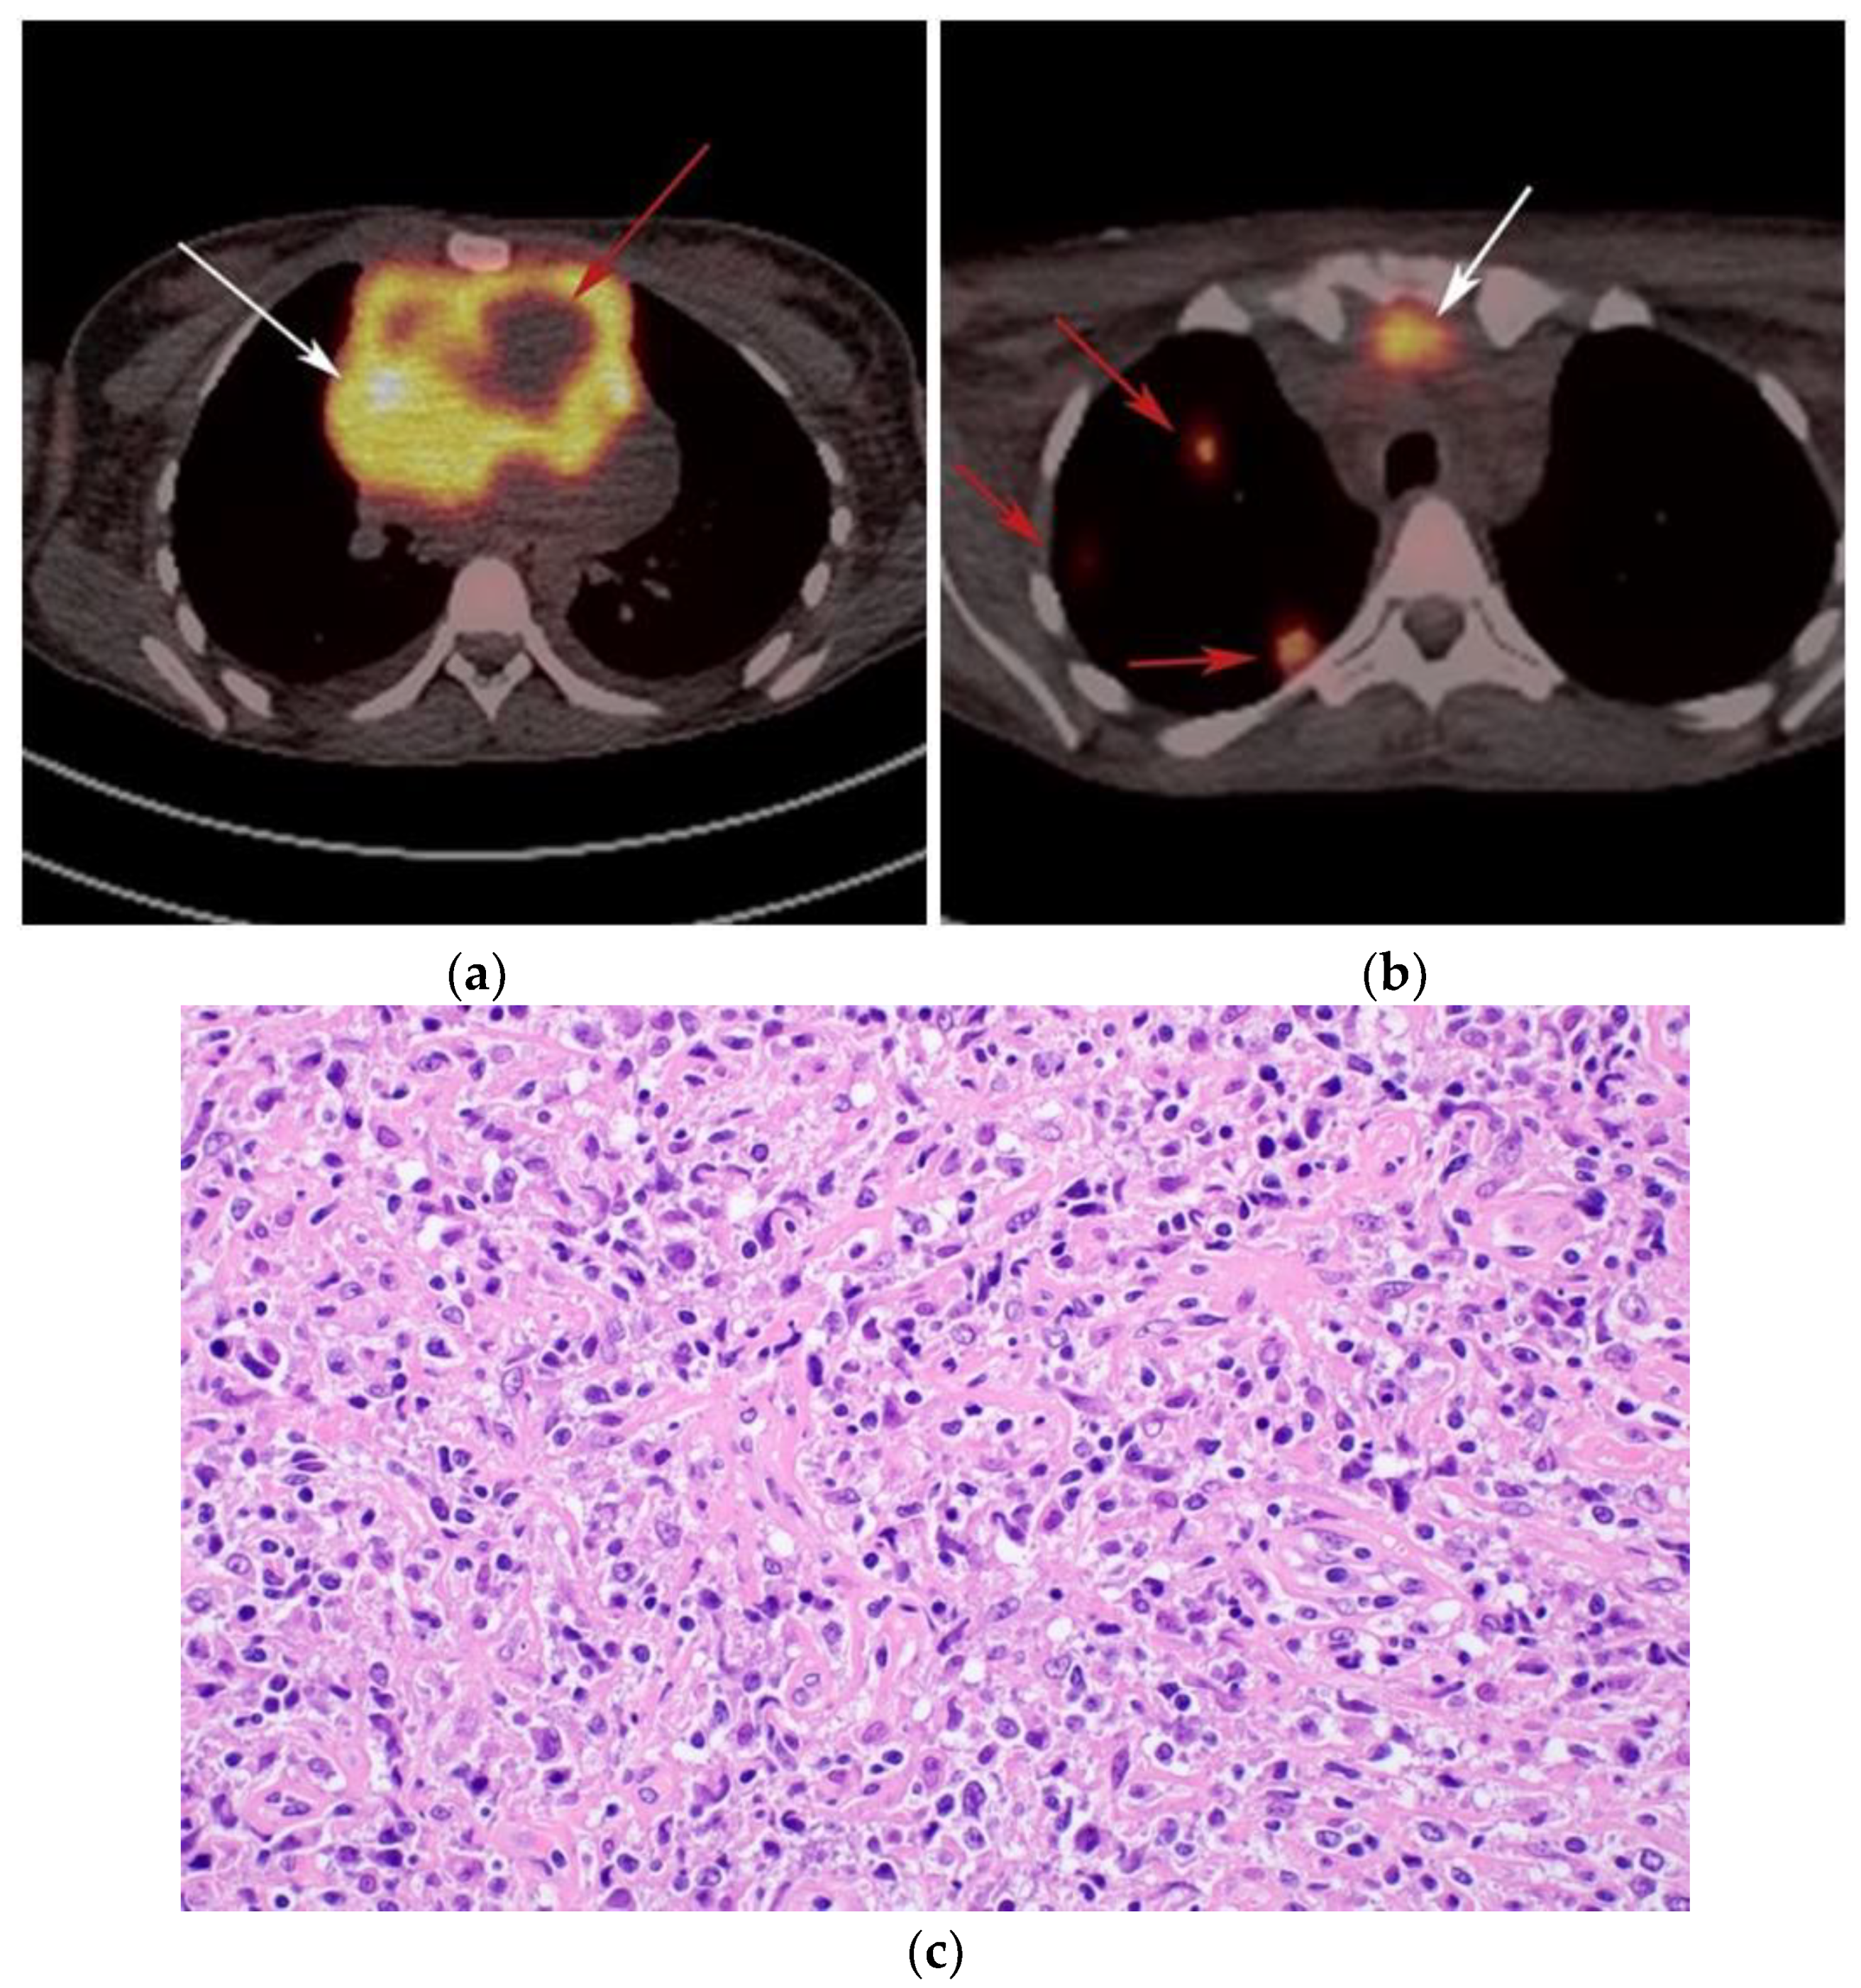

The use of 18F-FDG PET/CT is essential in the evaluation of patients with PMLBCL to reveal sites of disease not visible on CT and to provide more accurate staging and radiation field planning (Figure 6). 18F-FDG PET/CT may also be beneficial for restaging after chemotherapy and/or radiotherapy, or when relapse is suspected [34]. Negative 18F-FDG PET/CT after two or four cycles of chemotherapy has a negative predictive value and may predict excellent outcome in patients, achieving complete response without relapse. Patients who have residual activity equal to or higher than liver activity after immunochemotherapy treatment are more likely to relapse. In such instances, the addition of radiotherapy to the treatment regimen should be considered to avoid relapse in those high-risk patients. Relapse usually occurs within 1 year and is more likely to be widespread, involving distant extranodal sites such as the CNS, liver, kidneys, adrenal glands, GI tract, ovaries, and pancreas. Late relapses are very uncommon [35]. 18F-FDG PET/CT can also efficiently assess post-treatment response, differentiating between necrotic or fibrotic tissue and residual masses containing viable tumor [33,36]. There are various potential challenges to 18F-FDG PET/CT post-treatment implementation, including false-positive results secondary to thymic rebound hyperplasia, specifically seen in the young population. This can be limited by increasing the interval between treatment and imaging. Additionally, MRI can be helpful in those cases, and high signal on T1 in phase imaging with loss of signal on the out of phase sequences is consistent with thymic rebound hyperplasia (Figure 7 and Figure 8) [34,37].

Figure 6.

Imaging in a different patient with known diagnosis of primary mediastinal B-cell lymphoma. (a) Axial FDG PET/CT images show the hypermetabolic anterior mediastinal mass (white arrows), and there is also central areas of absent metabolic activity within the mass (red arrow), correlating with areas of fibrosis, a finding that is essential in prebiopsy planning to avoid false negative results. (b) Axial FDG PET/CT images show hypermetabolic right upper paratracheal nodes (white arrows) and several additional hypermetabolic pulmonary and pleural-based nodules within right upper lung (red arrows). (c) H&E section shows that the tumor is composed of large, atypical cells with reniform or multi-lobulated nuclei with abundant clear cytoplasm. Note the lymphoma cells are compartmentalized by the prominent sclerotic bands of fibrosis. (Original magnification 400x, H&E stain).